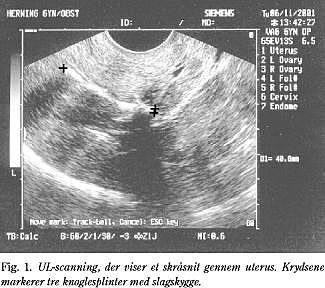

Patienten var 33 år og havde haft to fødsler samt en provokeret og tre spontane aborter i henholdsvis gestationsuge 10, 9 og 15. Ved den seneste abort blev patienten scannet i uge 13, hvor biparietaldiameteren svarede til 13 uger + 6 dage. På grund af formodning om urinvejsmisdannelse blev der aftalt en ny scanning 11 dage senere. Ved kontrolscanningen var fosteret dødt med begyndende sammenfald af caput. Uterus blev tømt med sug nummer 14 og skrabet med en stump curette, der blev ikke anvendt UL-scanning i forbindelse med udskrabningen. Knap fem måneder efter aborten blev kvinden henvist med menorrhagia. Der var samtidig graviditetsønske. Ved UL-scanning blev der set ekkogene strukturer beliggende intrauterint (Fig. 1 ). Ved efterfølgende hysteroskopi fandtes flade, hvidlige elementer med brusk- eller knoglekonsistens. Fem-seks stumper blev fjernet med en spiraltang. I isthmus uteri var der ligeledes et forkalket element, som man opgav at fjerne på grund af perforationsrisiko. Mikroskopien viste knoglesplinter og reaktivt endometrium. Man kunne ikke histologisk afgøre, om der var tale om føtal knogle eller dystrofisk ossifikation. Kvinden konciperede to måneder senere.

Knoglevævet påvirker endometriet på samme måde som en spiral med øget prostaglandinniveau (2, 3) og histologisk verificeret kronisk endometritis, hvorved såvel implantationsevnen som spermatozomotiliteten hæmmes med infertilitet og blødningsforstyrrelser til følge (4). Den kroniske endometritis angives også at være årsag til blødningsforstyrrelser (5). Andre beskrevne symptomer er nedre abdominalsmerter, dyspareuni, udflåd eller afgang af hårde elementer fra vagina (6, 7). Tilstanden kan være kompliceret af adhærencedannelse omkring tubae og fimbriae (4), pyometra (4) og penetration af uterus (7). Diagnosen stilles ved vaginal UL-scanning, hvor der findes et højekkogent, slagskyggegivende intrauterint beliggende materiale (3, 6). Knoglestykkerne vil almindeligvis kunne fjernes hysteroskopisk, men lejlighedsvis kan de dog være så dybt lejret i endo- eller myometriet, at man må afstå fra fuldstændig fjernelse på grund af perforationsfare. Der kan anvendes gonadotropin releasing hormone (GnRH)-analoger inden hysteroskopien, hvilket får endometriet til at skrumpe og dermed giver bedre oversigtsforhold (2). Hysteroskopien kan suppleres med laparoskopi, hvis perforationsrisikoen er stor (1). Prognosen for blødningsforstyrrelserne, smerterne og infertiliteten er hovedsagelig god efter fjernelse af knoglestykkerne (1, 6). Selv efter 13 års sekundær infertilitet er der beskrevet hurtig indtrædende graviditet efter behandling (4).